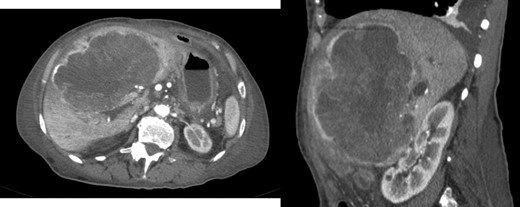

At 16 months, follow-up, local recurrence was identified on CT scan, showing an expansive heterogeneous lesion, below the stomach, with 7.4 cm of maximum diameter, showing no cleavage plan with the stomach (Fig. 4).

AP-CT – expansive heterogeneous lesion, with 7.4 cm, showing no cleavage plan with the stomach.